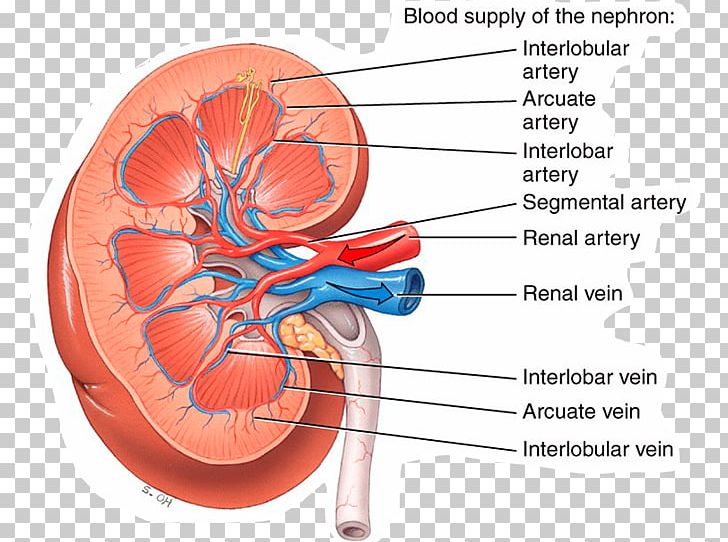

Principles Of Anatomy And Physiology Kidney Renal Artery

Principles Of Anatomy And Physiology Kidney Renal Artery